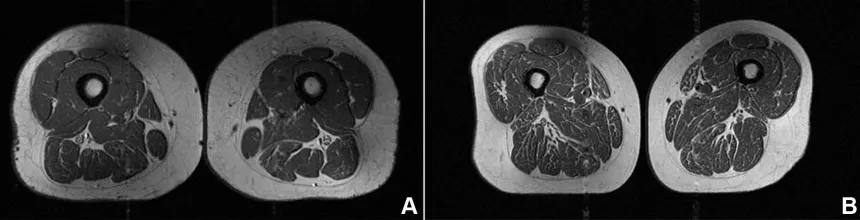

Posnetek magnetne resonance na naslovni fotografiji spominja na kos močno marmoriranega mesa, podobnega vrhunskemu zrezku z obilico drobnih maščobnih niti. A to ni zrezek, temveč stegno 62-letne ženske, ki je 87 odstotkov svojih letnih kalorij zaužila v obliki visoko predelane hrane.

Tudi 61-letna ženska, ki je bila vključena v študijo, je imela v stegenskih mišicah maščobo, a ta ni bila tako izrazita. Ultra predelana hrana je sestavljala približno 29 odstotkov njene diete. Kar je po besedah avtorice študije skrb vzbujajoče, so ti posamezniki že kazali poslabšano kakovost mišic, čeprav niso imeli osteoartritisa kolena. Sklepi so v tem primeru dodatno obremenjeni in lahko vodijo v kasnejše kronične bolečine v kolenih.

61-letna ženska (slika A), katere prehrana je bila v 29,5 odstotka primerov sestavljena iz visoko predelane hrane, je imela nekoliko višji ITM (32,6) in precej nižjo stopnjo telesne aktivnosti kot ženska na sliki B z ITM 31,8, katere prehrana je v 87,1 odstotka sestavljena iz ultra predelane hrane. Kljub temu je imela ženska z višjim deležem visoko predelane hrane v prehrani še vedno znatno več maščobnih vstavkov v mišicah. Na pojav te maščobe ni vplival vnos kalorij, temveč vrsta prehrane. Ni jasno, kako dolgo se mora človek prehranjevati na tak način, da se to zgodi, a povezava je zelo očitna, pojasnjujejo avtorji študije.